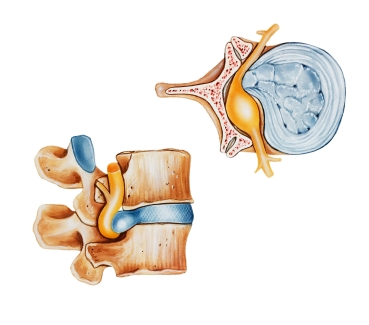

Также называется грыжи межпозвоночного диска или поврежденных дисков. Позвоночник состоит из костей (позвонков), разделенных желатиновых подушки (диски). Диски удерживается на месте с связок. Когда эти связки слезу, диски выступать в период между позвонками. Они торчали дисков может подтолкнуть на спинномозговые нервы, вызывая сильную боль и боль в руке или ноге обслуживают эти нервы. Порой выступ может привести к повреждению нервов и требует возникающих хирургического вмешательства.